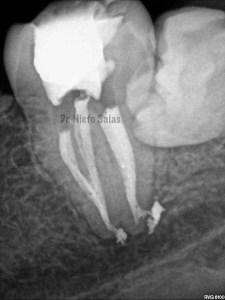

Bueno , ante esta piezas, que presentan una periodontitis apical crónica en la 4.7 y una pulpitis irreversible en la 3.7 nos disponemos a realizar le tratamiento de conductos.

Intentamos mantener la permeabilidad y la forma de  los conductos. Instrumentamos con Pathfile y Mtwo hasta un 25-6%.

(ORTO)                                                               (DISTO)

(MESIO)